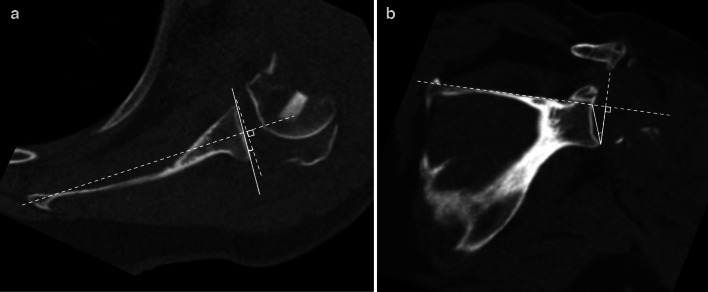

Materials and methods: Patients over the age of 18 who underwent rTSA for proximal humerus fractures from January 1, 2015 to October 31, 2023 at two university health system affiliated hospitals were included if they had a CT scan available for review and image reconstruction. Patients were excluded if a pathologic fracture was identified, surgery was performed greater than 6 weeks after the initial injury, surgery was a conversion or revision surgery, or if a glenoid fracture was present. Glenoid version and reverse shoulder arthroplasty (RSA) angles were measured by a musculoskeletal fellowship-trained radiologist and a shoulder and elbow fellowship-trained orthopaedic surgeon and averaged for final values. Glenoid morphologies were determined using the Walch and Favard classifications.

Results: A total of 53 patients with a mean age of 70.4 years (range 36.6-91.2) were included in this study, 84.9% of which were female. Walch A1 glenoid morphology was noted in 92.5% of patients, and Favard E0 morphology was present in 98.1% of patients. Median glenoid version was 3° of retroversion. Median RSA angle was 19°. Of note, 37.7% of patients had a RSA angle of ≥ 20°.